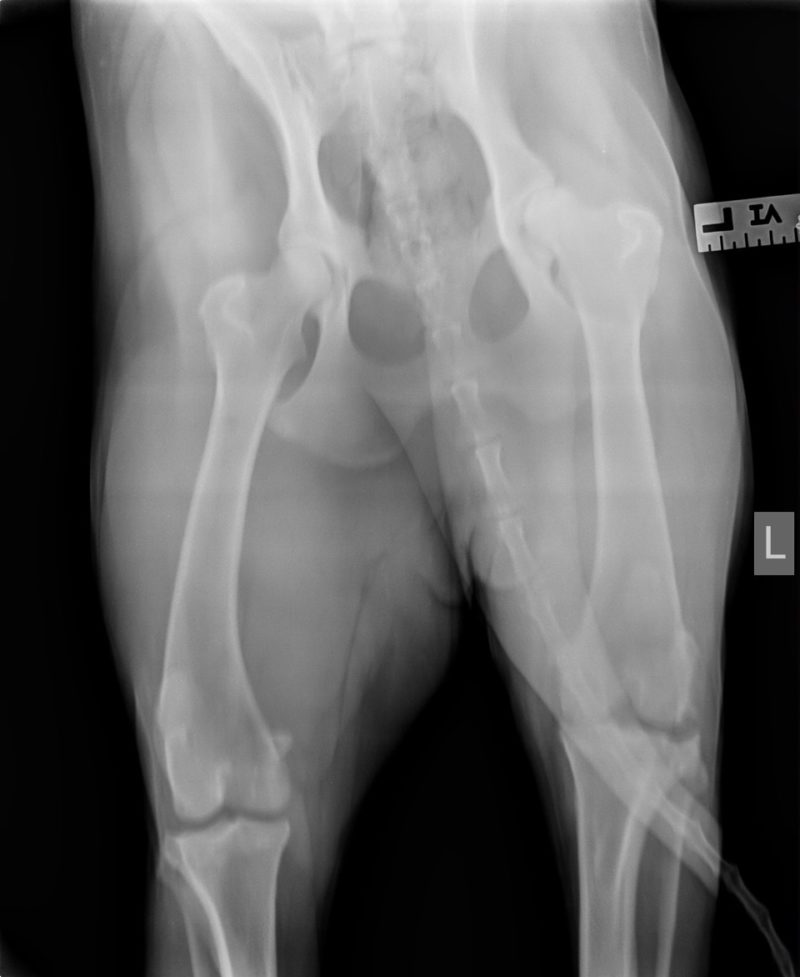

Die Röntgenaufnahmen des Haustierarztes vom linken Knie sowie des Knies und der Hüfte zeigen einen alten Kreuzbandriss (KBR) mit bereits hochgradiger Arthrose des Kniegelenks. Die Knie-Mechanik wird durch die Arthrose vermutlich mehr beeinträchtigt als durch den KBR. Weitere Röntgenbilder liegen nicht vor. Da Lea zudem sehr auffällig in der Wirbelsäule ist, haben wir auch hier Röntgenbilder angefertigt. Auf diesen sind ebenfalls hochgradige Arthrosen sowie ein Bandscheibenvorfall in der hinteren Brustwirbelsäule zu sehen. Das ist wohl momentan Leas hautsächliches Problem. Bei einer Kreuzbandriss-OP mit entsprechender Lagerung und anschließender Schonhaltung wäre die Wirbelsäulen-Problematik möglicherweise noch weiter verschlechtert worden. Das hätte im schlimmsten Fall sogar zu einer vollständigen Lähmung führen können. Zudem sind die mechanischen Beeinträchtigungen im Knie durch die hochgradige Arthrose mit einer Kreuzband-OP nicht aufzulösen. Bei einer Instabilität des Kniegelenks wäre selbstverständlich eine Operation des KBR notwendig. Sofern die Stabilität des Gelenks erhalten ist, können auch durch konservative Behandlungsmethoden oft sehr erfreuliche Ergebnisse erzielt werden. In Leas Fall wäre eine Entfernung der Verkalkungen innerhalb des Gelenks empfehlenswert, sobald sie für eine OP hinreichend stabil ist, da diese „Fremdkörper“ im Gelenk immer wieder Entzündungen auslösen können.